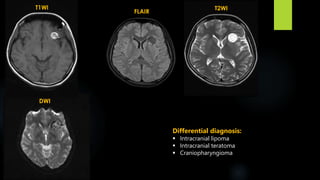

Intracranial Teratoma

 account for the largest proportion of fetal intracranial neoplasms

 divided into two broad categories:

- intra- and extra-axial

 Intra-axial teratomas present antenatally due to increasing head circumference; tend to occur

supratentorially

 Extra axial teratomas usually present in childhood or early adulthood; commonly arise in the

pineal or suprasellar regions; obstructive hydrocephalus, Parinaud syndrome

Intracranial Teratoma (contd.)

 CT:

 Intracranial teratomas are often seen as large lesions at presentation

 tumours typically demonstrating a mixture of tissue densities and signal intensity

 demonstrate at least some fat and some calcification, which is usually solid / "clump-like"

 They usually have cystic and solid components, contributing to an irregular outline.

 Solid components demonstrate variable enhancement

 MRI:

 T1 - hyperintense components due to fat and proteinaceous/lipid rich fluid; intermediate

components of soft tissue; hypointense components due to calcification and blood products

 T1 C+ (Gd) - solid soft tissue components show enhancement

 T2 - again mixed signal from differing components

Differential diagnosis:

sPNET

ATRT

Choroid plexus carcinoma

Intracranial lipoma

Intracranial dermoid

Craniopharyngioma